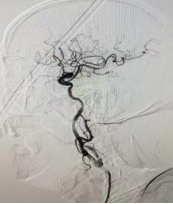

赶到时,初步检查提示“左侧颈内动脉闭塞性脑梗死”。县医院无法开展颈内动脉介入开通手术,必须立即转往西安。我一边快速完善术前评估、一边告知家属病情及转诊风险,一边联系我院介入团队做好术前准备,同时协调120救护车,全程陪同转诊。

12点,救护车顺利抵达我们医院,我陪同患者,对接我科介入团队,详细说明患者病情、转诊途中情况及前期处理措施,协助完善术前检查。12时24分,颈内动脉介入开通手术正式开始,随着我手中的导丝精准穿过血管闭塞段,取出长节段阻塞血栓,闭塞的血管逐渐恢复通畅,监护仪上的生命体征趋于平稳,我悬着的心终于落了下来。手术结束后,王爷爷家属红着眼眶再三道谢。所有的奔波与疲惫,都在这一刻有了最好的归宿。